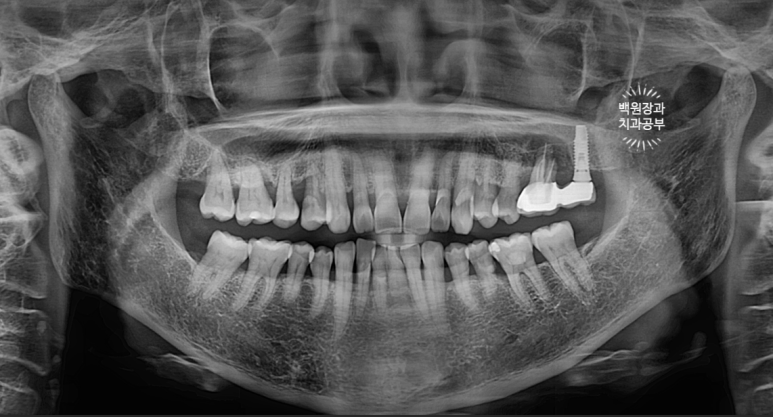

왠걸! 이런 보철물을 내가 직접 보게 되다니~

하나는 자연치아, 하나는 임플란트가 한 개의 보철물로 연결되어 있더라구요.

정확히 브릿지 (bridge)라고 부르지는 않지만, splinted crown 이라고 부릅니다.

교수님들 말씀이 맞았네요... 결국 자기 치아가 완전히 고장나버렸고,

주변은 염증이 가득 형성되서 잇몸뼈가 모두 사라져 버렸습니다.

너무 많이 뼈가 파괴되어 임플란트 심기가 어려워

처음 오셨을 때 입 안 사진으로 보면, PFM 크라운 두 개가 붙어있는 형태.

즉, splinted PFM crown 형태로 제작이 되어 있었어요.

추측컨데... 수술했던 임플란트 크라운이 너무 짧으니 잘 떨어질까봐 앞에 치아와 연결한게 아닐까 싶었습니다.

여튼.. 상부 보철물을 갈아서 뜯어내니, 여지없이 자연치는 쑥 빠져버렸습니다. ㅠㅠ